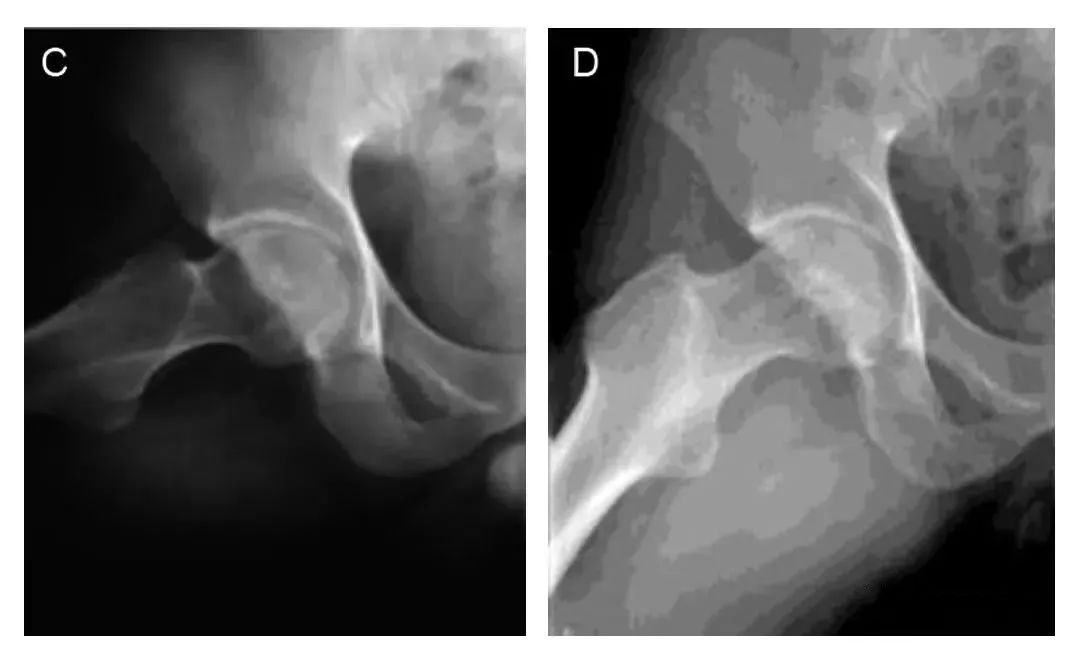

图中A和C:典型病例术前正位和蛙式位X射线片,

股骨头内不规则高密度影;

图B和D:典型病例术后7年正位和蛙式位X射线片,

股骨头外形规整,无塌陷。